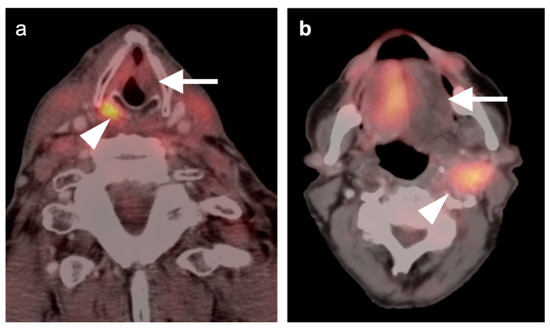

2.3. Nasopharyngeal Carcinoma

- Mohandas, A.; Marcus, C.; Kang, H.; Truong, M.-T.; Subramaniam, R.M. FDG PET/CT in the management of nasopharyngeal carcinoma. AJR Am. J. Roentgenol. 2014, 203, W146–W157. [Google Scholar] [CrossRef]